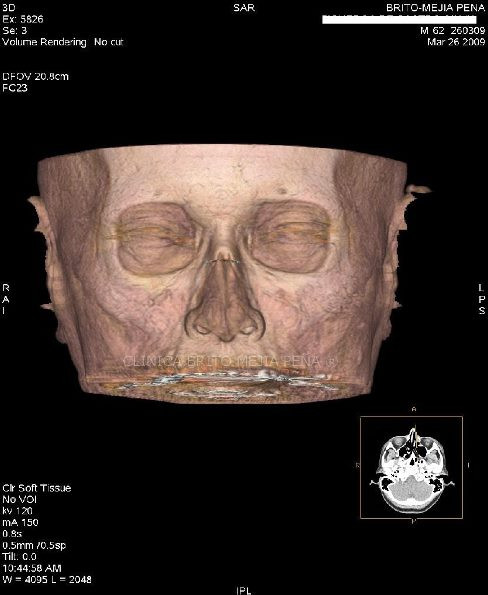

Cabeza y Cuello 2

Envíado por BMP Imágenes Diagnósticas

BMP Imágenes Diagnósticas